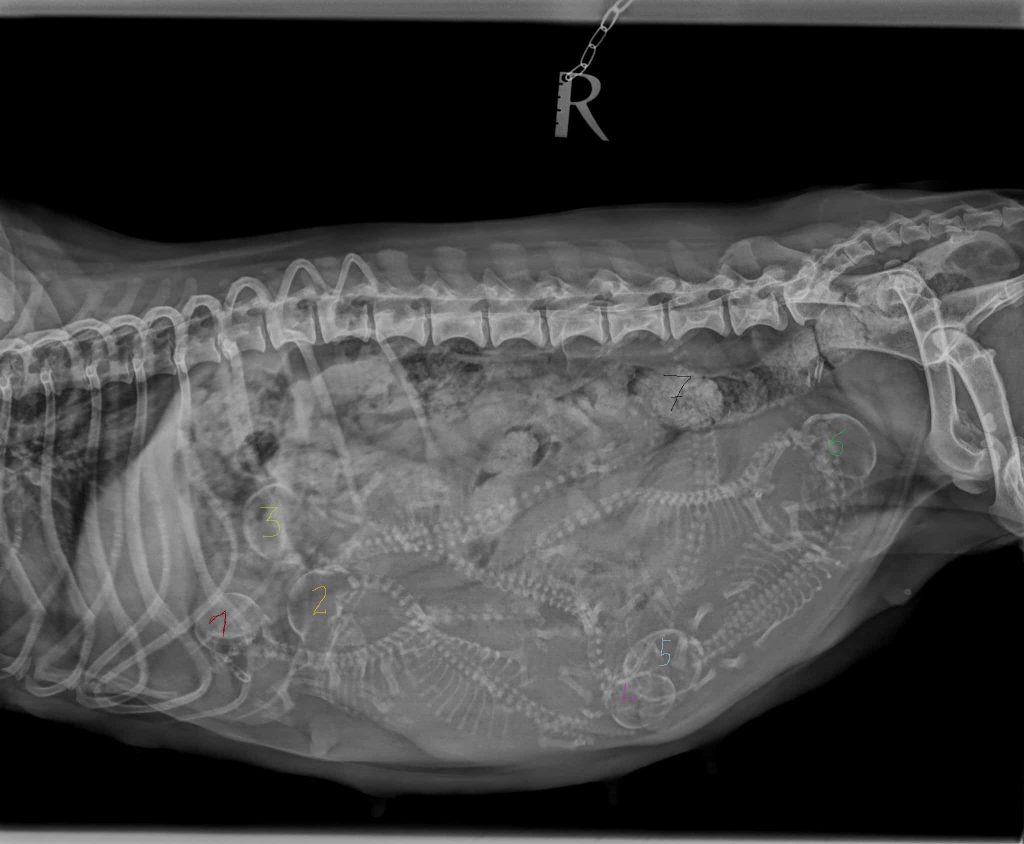

natürlich NICHT den TV Sender sondern den P Wurf mit 7 Welpen